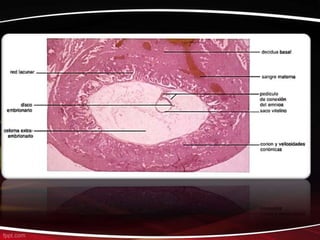

El documento describe las principales etapas del desarrollo embrionario humano desde el día 8 hasta la semana 8, incluyendo la formación del tubo neural, el corazón y los órganos internos, y el desarrollo progresivo del cuerpo y las extremidades.